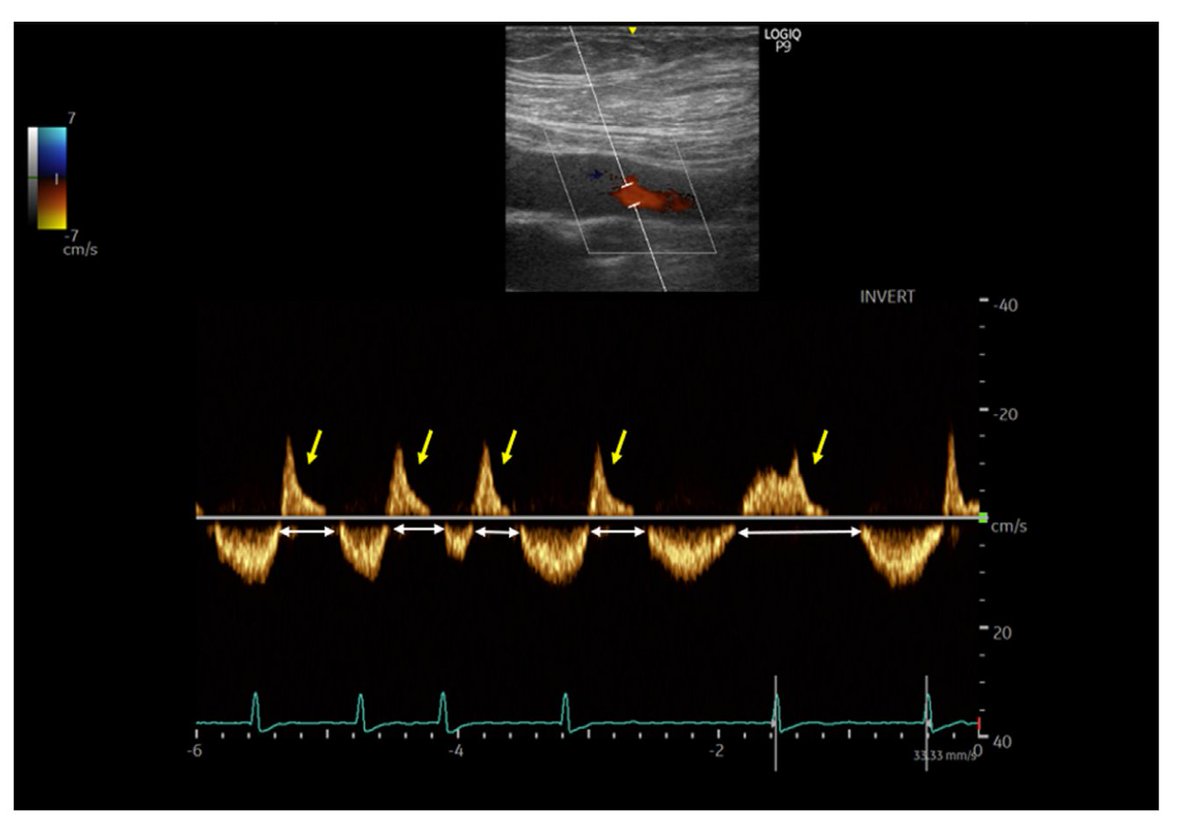

The femoral vein spectral display demonstrates a highly pulsatile waveform with significant flow interruptions (white arrows) and prominent retrograde waves above the baseline (yellow arrows), suggestive of severe venous congestion.

Antegrade femoral vein flow velocity representing vein flow from the periphery to the right side of the heart is 30 cm/s, whereas retrograde velocity of 35 cm/s represents systolic flow reversal, right ventricular dysfunction

Femoral vein Doppler pulsatility in venous congestion Serial femoral vein Doppler in a patient with severe venous congestion, and after 4 days of diuresis 1 . Femoral vein flow is biphasic with an important retrograde component

Normal femoral vein flow Doppler for comparison. Note the respiratory modulation and wide monophasic negative vein flow velocity representing antegrade vein flow with minor retrograde vein flow components.